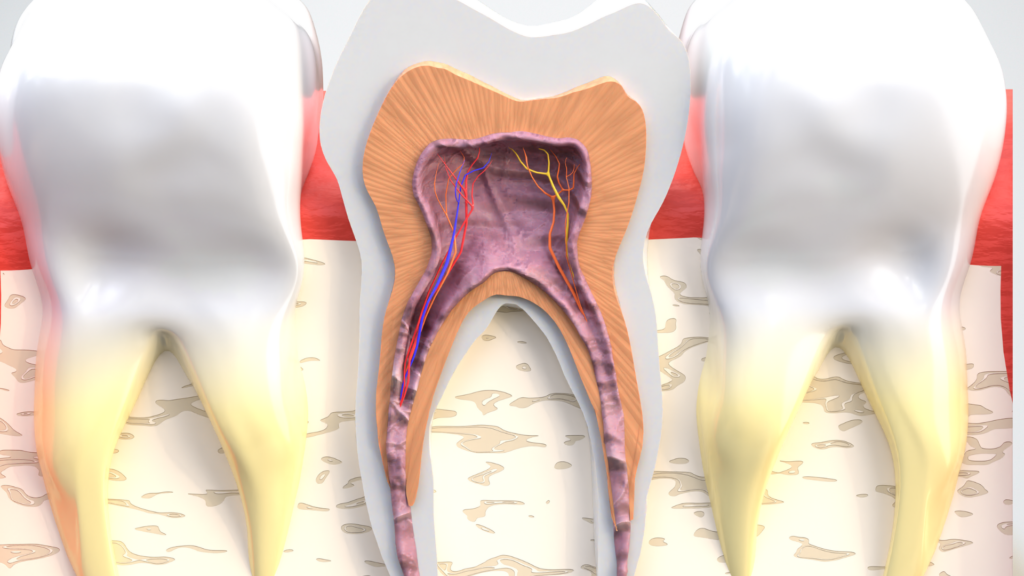

Сломанный зуб означает нарушение структурной целостности зуба. Обычно это происходит в результате травматического воздействия на зубы, применения чрезмерной силы или прогрессирования кариеса во рту.Зубные переломы не только наносят физический ущерб, но и могут серьезно угрожать здоровью зубов. Такие травмы могут возникать в разных местах, от корня зуба до его верхушки.

Зубные переломы, как правило, можно разделить на три основные категории: трещины, полные переломы и осколочные переломы. Трещины в зубах, как правило, представляют собой поверхностные повреждения и чаще всего сопровождаются слабо выраженными симптомами.Однако, если он проникает до внутренней части зуба, часто возникает вопрос, вызывает ли перелом зуба боль во рту. Полные переломы — это разлом зуба на две части, и в этом случае симптомы, такие как боль и воспаление, обычно становятся более выраженными. Частичные переломы возникают в результате разлома зуба на несколько частей, и такие переломы зачастую затрудняют лечение зуба.

Вопрос о том, вызывает ли сломанный зуб воспаление, возникает в случае поражения слизистой оболочки или внутренней части зуба. Воспаление внутренней части зуба может создать серьезные проблемы для здоровья зубов и потребовать немедленного применения соответствующих методов лечения. В таких случаях часто задают вопрос о том, как лечить сломанный зуб.Методы лечения могут варьироваться в зависимости от типа перелома, поэтому важно получить консультацию специалиста.

Сломанный зуб — это серьезное состояние, угрожающее здоровью зубов и обычно вызывающее сильную боль. Сломанный зуб может повредить его внутреннюю структуру, что приводит к боли различной интенсивности и типа.Зубные переломы обычно проявляются в виде чувствительности, покалывания или острой боли. Вопрос о том, болит ли сломанный зуб, встречается довольно часто, и ответ на него положительный, поскольку при переломе зуба, повреждении нервных и сосудистых структур зуба, боль неизбежна.

Интенсивность боли может варьироваться в зависимости от формы и места поломки зуба, а также от болевого порога человека. Например, поломка в корневой части зуба может вызвать более сильную боль, чем поломка на внешней поверхности.Вместе с тем, в результате перелома зуба может возникнуть воспаление; воспаление может усилить боль, увеличивая напряжение и давление в этой области. Вопрос о том, вызывает ли перелом зуба воспаление, также является важным моментом, и ответ на него снова положительный; поврежденная структура переломанного зуба увеличивает риск инфекции.